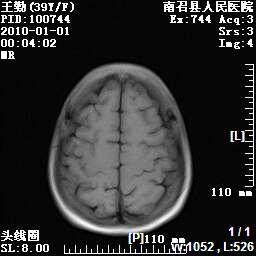

以下是引用随光逐影在2010-1-22 9:03:00的发言:[br]考虑左侧中颅窝(蝶骨翼区)脑膜瘤侵犯蝶骨翼并突入左侧眼眶。

以下是引用水过无痕在2010-1-22 14:55:00的发言:[br]一、定位:颅外占位;二、定性:恶性可能性大;三、组织来源:来源于左侧眼外直肌或其他部位;考虑为:横纹肌肉瘤>转移瘤>脑膜瘤.